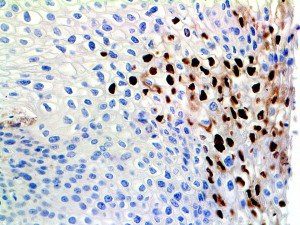

It is the ICU physician who is most likely to witness one of the deadliest manifestations of the abnormal immunological response, the cytokine storm syndrome (CSS). This response is also referred to by some as the cytokine release syndrome (CRS). CSS is characterized by continuous activation and expansion of macrophage and lymphocyte populations, which secrete large amounts of cytokines, causing the cytokine storm. This massive cytokine release is akin to hemophagocytic lymphohistiocytosis (HLH) disease, a syndrome characterized by initial unchecked and persistent activation of cytotoxic T lymphocytes and NK cells.

Clinical and laboratory manifestations of HLH include fever, enlarged liver and/or spleen, neurologic dysfunction, coagulopathy, liver dysfunction, cytopenias (i.e., low levels of erythrocytes, leukocytes, and/or platelets), hypertriglyceridemia, hyperferritinemia, hemophagocytosis, and eventually diminished NK cell activity as the immune system becomes progressively paralyzed. HLH can be familial (primary HLH) or secondary to another disease process (sHLH), such as rheumatic disease, in which it is referred to as macrophage activation syndrome (MAS, characterized by elevated ferritin).